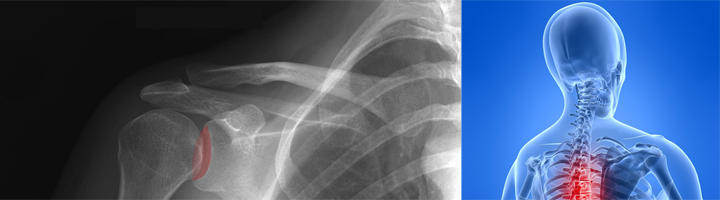

Prothèse d’épaule imprimée en 3D

La deuxième nouveauté récente du secteur médical nous vient des Pays-Bas, à l’hôpital Rijnland où le chirurgien orthopédiste Cornelis Visser a implanté une cavité glénoïde (cavité recevant la tête d’un os) dans l’épaule d’un patient. Là aussi, l’implant imprimé en 3D s’adapte parfaitement à l’anatomie du blessé grâce à un scanner préopératoire, permettant de retrouver presque tous les mouvements de l’articulation. Le docteur explique que grâce aux techniques liées à l’impression 3D, il y a moins d’improvisation durant l’opération et les implants durent plus longtemps. La prothèse sur-mesure s’installe en effet naturellement et force moins avec les autres os.

Implant vertébral imprimé en 3D

C’est au Docteur français Vincent Fière de l’hôpital Jean Mermoz à Lyon que l’on doit cette première mondiale de pose d’implant vertébral sur-mesure imprimé en 3D. Il s’agit plus précisément de la cage d’ostéosynthèse inter-somatique qui a été réalisée par la société Medicrea spécialisée dans le développement de nouvelles technologies chirurgicales pour le traitement des pathologies de la colonne vertébrale. En se basant sur les images d’un scanner du patient, ils ont pu fabriquer un implant correspondant parfaitement aux détails morphologiques de la colonne à traiter et même de corriger des problèmes de hauteur discale et de lordose lombaire. Suite au succès de l’opération, Medicrea a souhaité breveter cette nouvelle méthode d’implant osseux et imagine déjà des implants renforcés en matériaux biocompatibles tels que le polymères ou le titane.